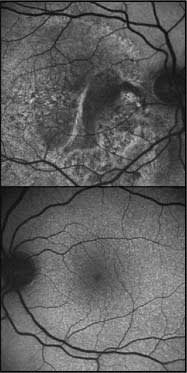

Figure 3. Usher syndrome in a woman 34 years of age. Autofluorescence of the right eye shows RPE atrophy underneath degenerated rods. Note the cystoid macular edema, a common complication of rod-cone dystrophies.

Retinitis pigmentosa, also known as rod-cone dystrophy, has both genetic and allelic heterogeneity (Figures 2 and 3).25 RP inheritance can be autosomal dominant, autosomal recessive, or X-linked recessive, and there is genetic heterogeneity even within each group. Retinal degeneration slow (RDS) protein and retinal-specific adenosine triphosphate (ATP)-binding cassette transporter (ABCA4) are examples of allelic heterogeneity in that they can cause macular dystrophy in some patients and cone-rod dystrophy in others.

The age of onset of RP is variable and patients do not always present with the classic triad of intraretinal pigment migration, optic nerve pallor, and attenuated vessels (Figure 3). In general, patients who develop symptoms at younger ages have worse prognoses, and dominant disease has a less severe natural history with later onset when compared to X-linked and recessive variants. In RP, patients with normal VA and smaller, higher-density autofluorescent rings correlate with worse-pattern ERGs. This represents a shrinking area of photoreceptor function as disease progresses.14,15 In time, VA declines, visual fields coalesce to give the classical peripheral ring scotoma, and posterior subcapsular cataracts or cystoid macular edema (CME) may develop (Figure 3).